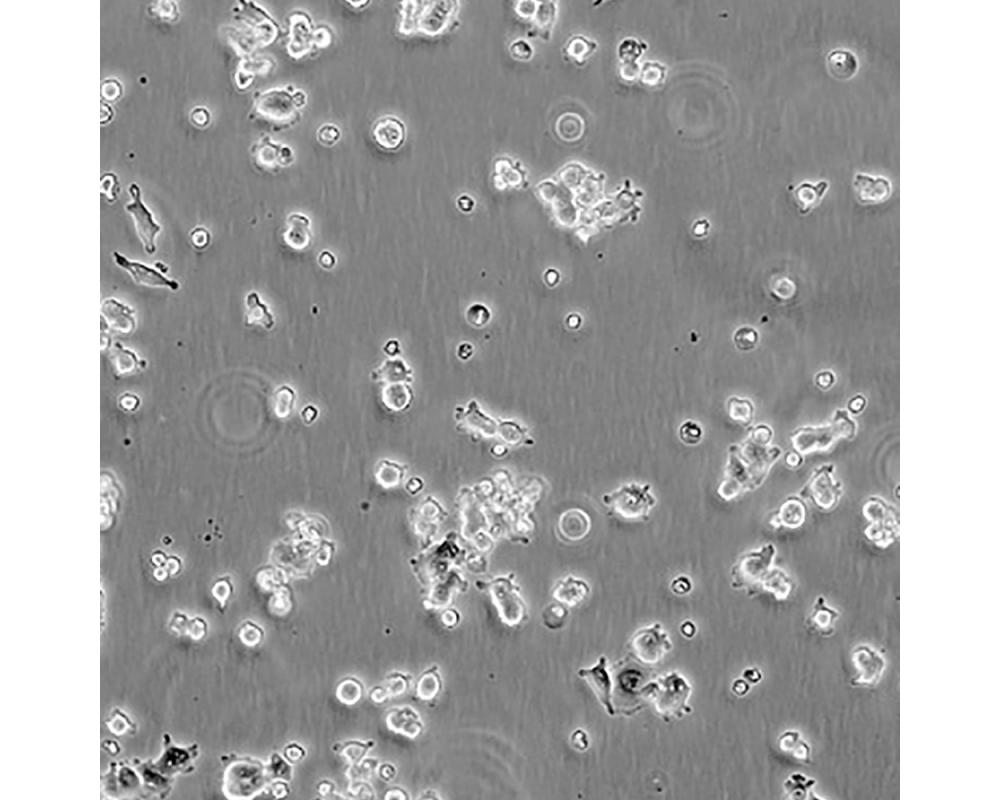

中文名稱 人肺腺癌細胞

組織來源 肺腺癌;男性

生長特性 貼壁

培養基 1640,90%;FBS,10%;雙抗。

培養條件 Atmosphere: Air, 95%; CO2, 5%。Temperature: 37℃